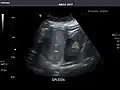

Spleen